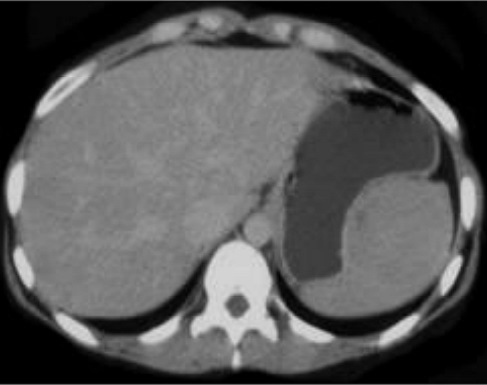

Image radiologique TDM une

splenomegalie par infection mononucleose . La rate

est volumineuse , tres epais , sa diamètre

antero-posterieure depasse plus de 10,5cm |